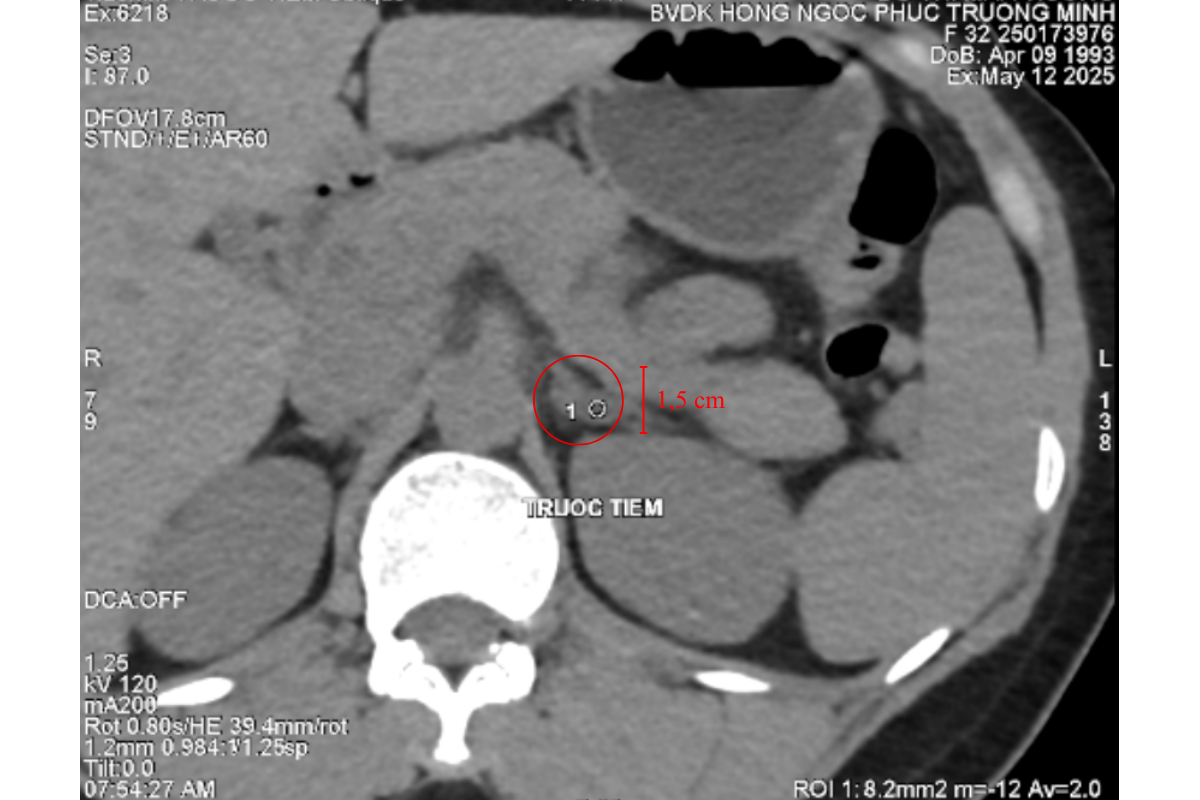

Trong một chuyến công tác tại Hà Nội,chị P quyết định đến thăm khám tại Bệnh Viện Đa Khoa Hồng Ngọc. Từ khai thác tiền sử và các triệu chứng lâm sàng, các bác sĩ nghi ngờ chị P mắc u tuyến thượng thận, một bệnh lý về nội tiết rất hiếm gặp, có thể thường xuyên gây tăng huyết áp đột ngột. Kết quả chụp cắt lớp vi tính ổ bụng không nằm ngoài dự đoán, chị P có 1 khối u tuyến thượng thận kích thước 1,5cm nằm ở tuyến thượng thận trái. ThS.BS CKII Trịnh Minh Thanh người trực tiếp thăm khám cho bệnh nhân nhận định: “Đây chính là nguyên nhân khiến bệnh nhân thường xuyên bị tăng huyết áp nội sinh, kéo dài suốt một thời gian nhưng chưa được phát hiện”.

Khối u tuyến thượng thận trái, kích thước 1,5cm

Dù kích thước chỉ 1,5cm khối u tuyến thượng thận nằm sâu trong khoang sau phúc mạc, gần đuôi tụy vị trí hẹp và gần nhiều cấu trúc quan trọng như mạch máu lớn và thận. Phẫu thuật nội soi trong trường hợp này đòi hỏi bác sĩ phải xác định chính xác vị trí khối u, kiểm soát tốt vùng mổ và thao tác khéo léo để tránh tổn thương mô lành. Với sự hỗ trợ của hệ thống nội soi hiện đại, sau 2 giờ ca mổ diễn ra an toàn, ít xâm lấn và hỗ trợ bệnh nhân hồi phục nhanh chóng.